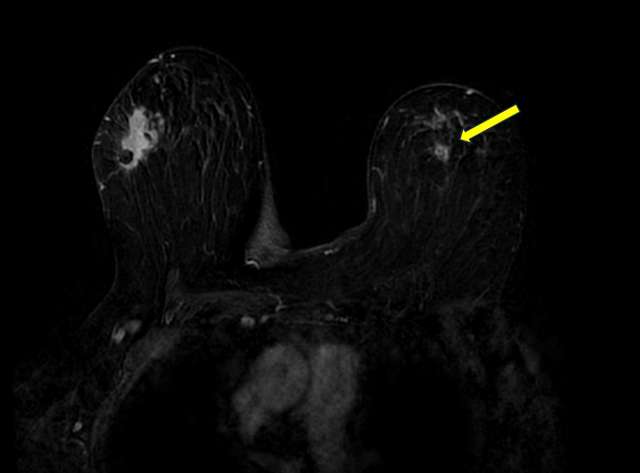

There is limited data regarding the MRI appearance of ALH. One study showed that most cases of ALH presented as NME, however given the limited sample size this may not reflect the true distribution of MRI appearances.4